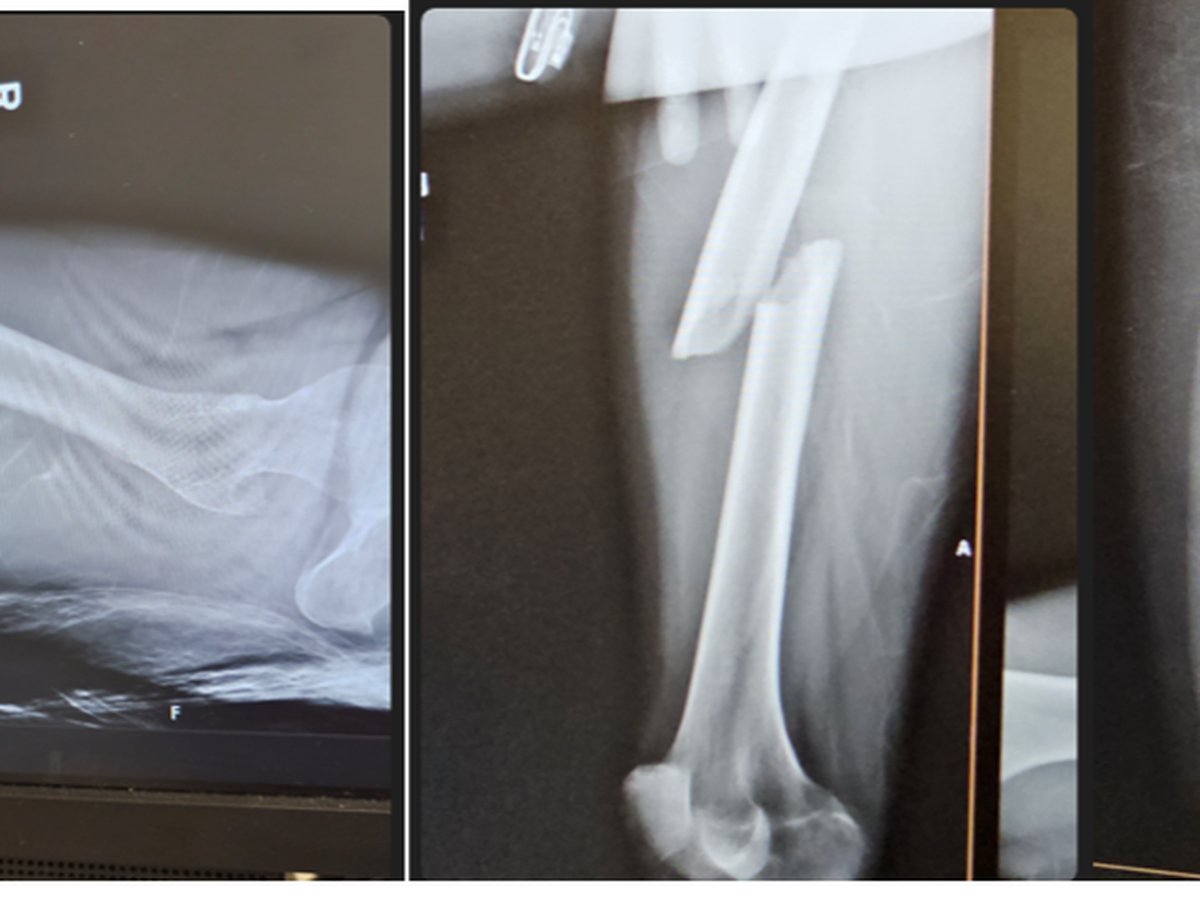

Fatima’s life took an unexpected turn when she was involved in a severe car accident. The accident left her with major injuries, including fractured bones. The physical pain she endures daily is unimaginable, and it has taken a tremendous toll on her both physically and emotionally.